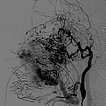

Lateral view of a digital subtraction angiography after contrast injection into the left external carotid artery. The AVM is visible as a diffuse, reticular net-like nidus with direct, strong venous outflow centrally in the left cheek (fast-flow malformation).

Lateral view, DSA after contrast injection in the left internal carotid artery. There is also a massive supply to the nidus of the AVM from the internal carotid artery, mainly via the ophthalmic artery and the meningohypophyseal trunk.

This complicates embolization therapy considerably.

DSA, anterior-posterior view, after injection into the right common carotid artery. The nidus of the AVM on the left cheek is also supplied from the contralateral right external carotid artery and right facial artery.